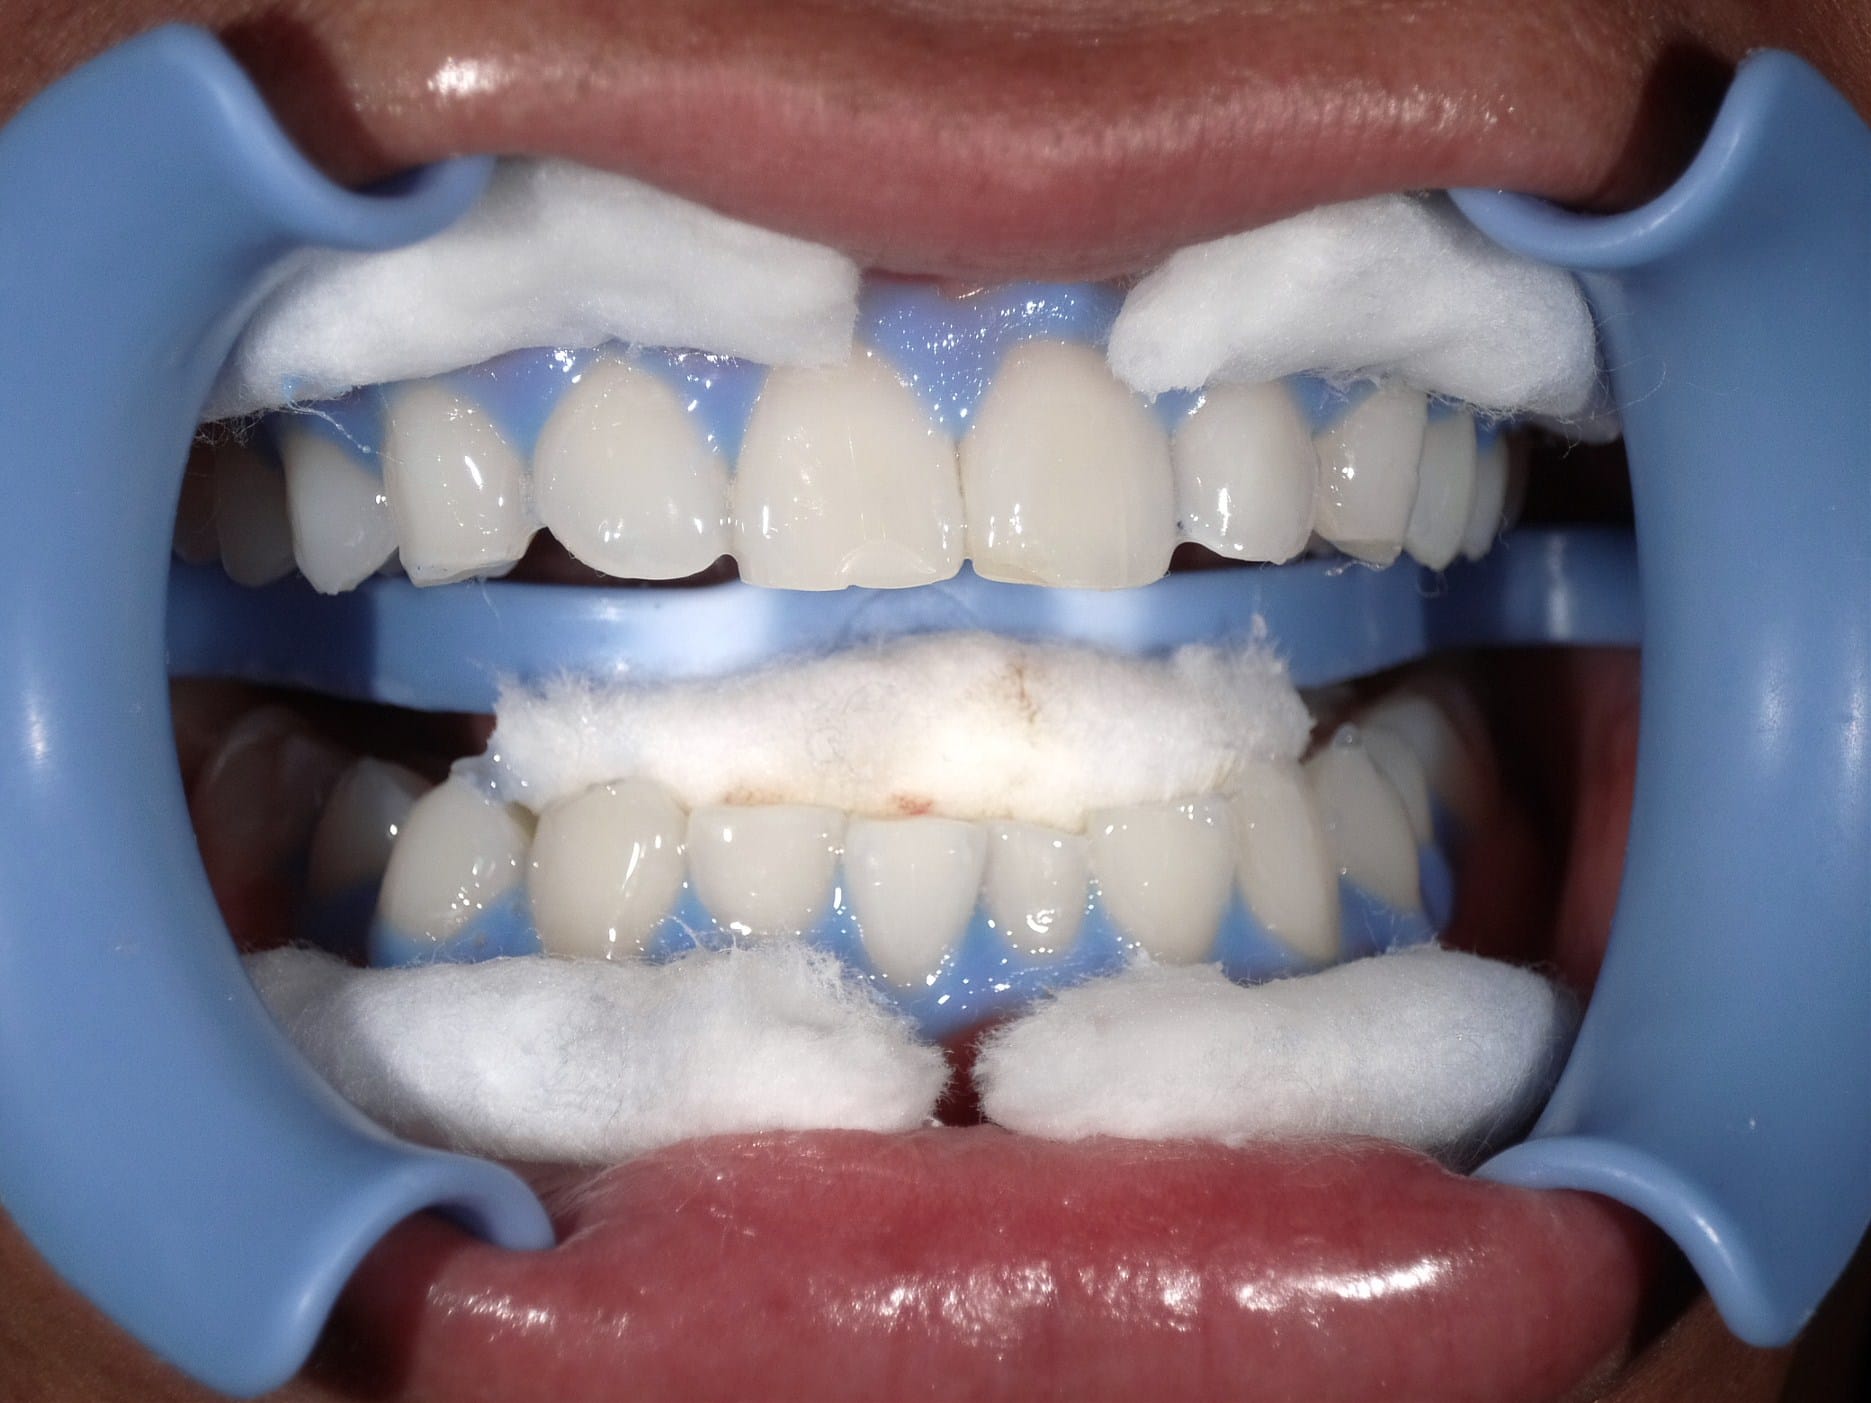

Case022 – インプラント

広島からの患者様です。

前歯を綺麗にしたい。インプラントをしたい。

という主訴で東京の歯医者をいろいろ調べて当院を選んでくださいました。

毎回、遠い中しっかり通ってくださり、選んで頂けた嬉しさと、その気持ちに応えたいという想いで診療させて頂きました。

前歯はご希望のお色でラミネートベニアでは出せない透明感のあるセラミックに上下左側7はインプラントをさせて頂きました。

左上は破折で温存不可。

骨も少なかったので、サイナスリフトも行い計五回の来院で被せ物を入れさせて頂きました。

左下は前回のクリニックでの埋入位置が深すぎて食べカスも毎回詰まる、セルフメンテナンスではら汚れも取れない。インプラント周囲炎にもなっていたので、一度前のインプラントを除去し、そこから新しくインプラントを埋入し、診療させて頂きました。

インプラント、歯並び、審美歯科にご興味のある方はいつでも相談にお越しください。

担当 理事長 佐藤 悠野